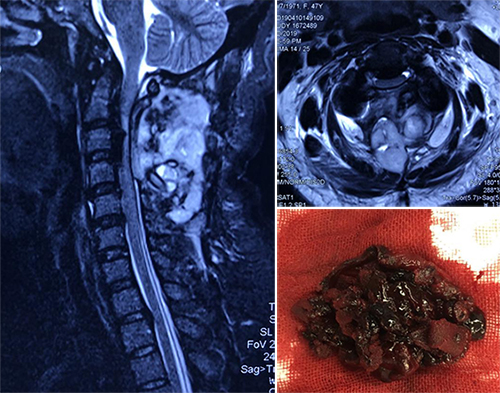

患者发病急,症状重,谭炳毅副主任医师根据多年工作经验,建议行颅脑、颈部MR检查,一时间明确诊断的希望寄托到磁共振上。磁共振诊断显示,其颈部切口内血肿压迫了脊髓,造成了四肢软瘫。

“立马手术!”医生作出决定,并马上与手术室、急诊ICU联系协调。手术室与急诊ICU鼎力相助,在10分钟内将亓女士送入了手术室,争取到宝贵的时间,让手术医师第一时间为患者解除压迫,清除血肿。

当晚21:30,手术终于成功完成!术后,亓女士苏醒了,四肢也恢复了活动,所有医护人员长舒一口气,并将好消息第一时间告知患者家属。为了安全起见又将患者送入ICU继续监护治疗。

在术后第二天,亓女士四肢活动良好。虽然双手仍感觉有点麻木,但言语、神志完全正常,并顺利转回病房。

接下来,亓女士的恢复情况一天比一天好,术后3天就能下地活动,并无不适,完全可以自己行走,步态良好,最终康复出院。